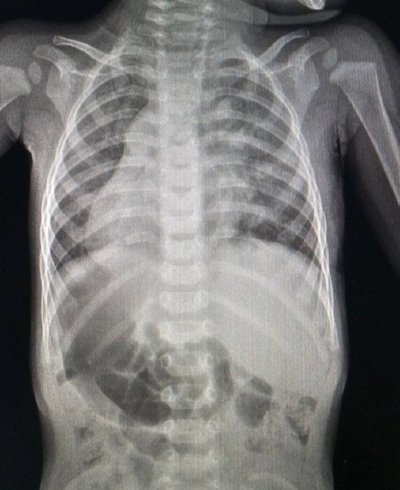

Дем’ян народився із дзеркальним розташуванням внутрішніх органів. Це означає, що його серце, селезінка і підшлункова є справа, а печінка і, до прикладу, апендикс навпаки — зліва. Тобто, абсолютно всі органи грудної клітки та черевної порожнини розташовані протилежно. За словами лікарів, таке трапляється вкрай рідко, але при цьому вважається варіантом анатомічної норми.

Рентген хлопчика. Пресслужба Першого ТМО Львова